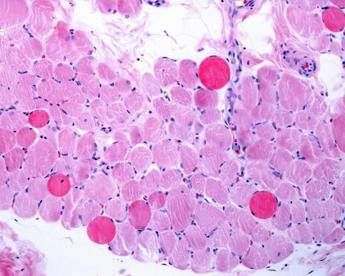

(Adnkronos) – Sono positivi i risultati di un'analisi dei dati a lungo termine – comprese le prime valutazioni dello studio multicentrico in aperto Guardian, attualmente in corso – che valuta Agamree* (vamorolone) in pazienti affetti da distrofia muscolare di Duchenne (Dmd). Lo annuncia in una nota Santhera Pharmaceuticals, precisando che l'analisi ha incluso pazienti mai trattati con corticosteroidi e che hanno iniziato il trattamento con Agamree tra i 4 e i 7 anni di età nell'ambito di studi clinici, proseguendo poi attraverso vari programmi di accesso tra cui lo studio Guardian. Sono stati analizzati i dati di un massimo di 110 pazienti, con un numero variabile in base alla disponibilità delle informazioni. In questa analisi i pazienti avevano ricevuto il trattamento per un massimo di 8 anni, con un follow-up mediano di circa 5 anni. La maggior parte dei pazienti ha mantenuto dosi elevate (4-6 mg/kg/giorno) in contesti clinici di real world durante il periodo di osservazione. I risultati mostrano che i pazienti trattati con vamorolone hanno mantenuto la funzione motoria durante il follow-up prolungato, dimostrando un'efficacia duratura del trattamento misurata in base al tempo di perdita della deambulazione paragonabile a quella dei corticosteroidi standard (p=0,91). Nelle analisi di sottogruppi prestabilite non sono state osservate differenze rispetto al deflazacort o al prednisone assunti quotidianamente. I dati – riporta l'azienda – continuano a confermare un profilo di sicurezza e tollerabilità differenziato rispetto ai corticosteroidi tradizionali. I pazienti trattati con Agamree hanno registrato un tasso significativamente inferiore di fratture vertebrali (p=0,0061), hanno mantenuto una crescita normale senza il rallentamento osservato con i corticosteroidi standard (p